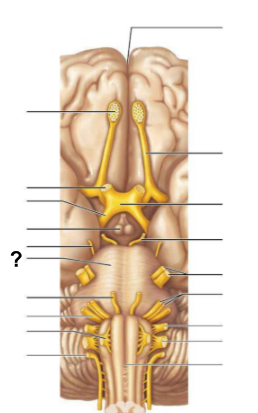

From the lateral ventricles, CSF flows through which structure, labeled “?”, to reach the third ventricle?

Interventricular foramen